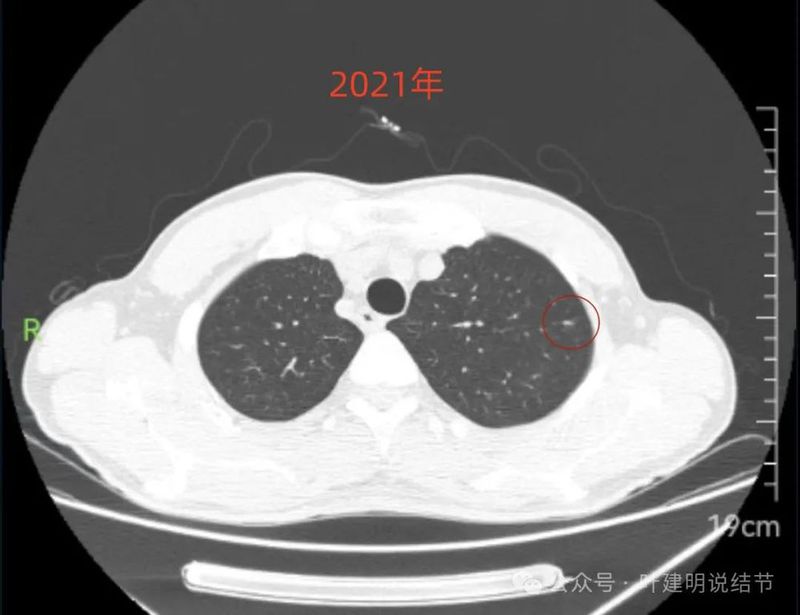

2021年6月右中叶病灶,较前无明显变化。

病灶上缘即偏实性,非圆形或类圆形。

边上有少许淡面模糊的磨玻璃成分。

轮廓欠清,瘤肺边界也不清晰。